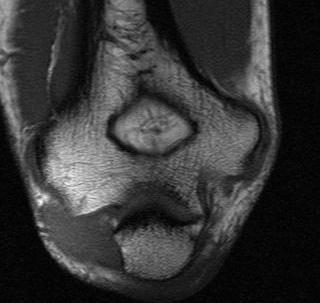

Elbow

- enters the cubital tunnel between the medial epicondyle and the olecranon

- running on MCL

- covered by osbourne's ligament